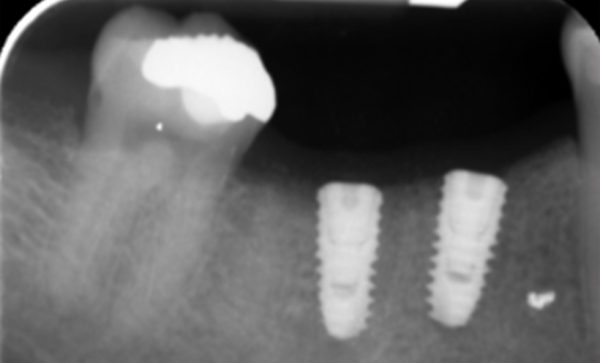

Case 10